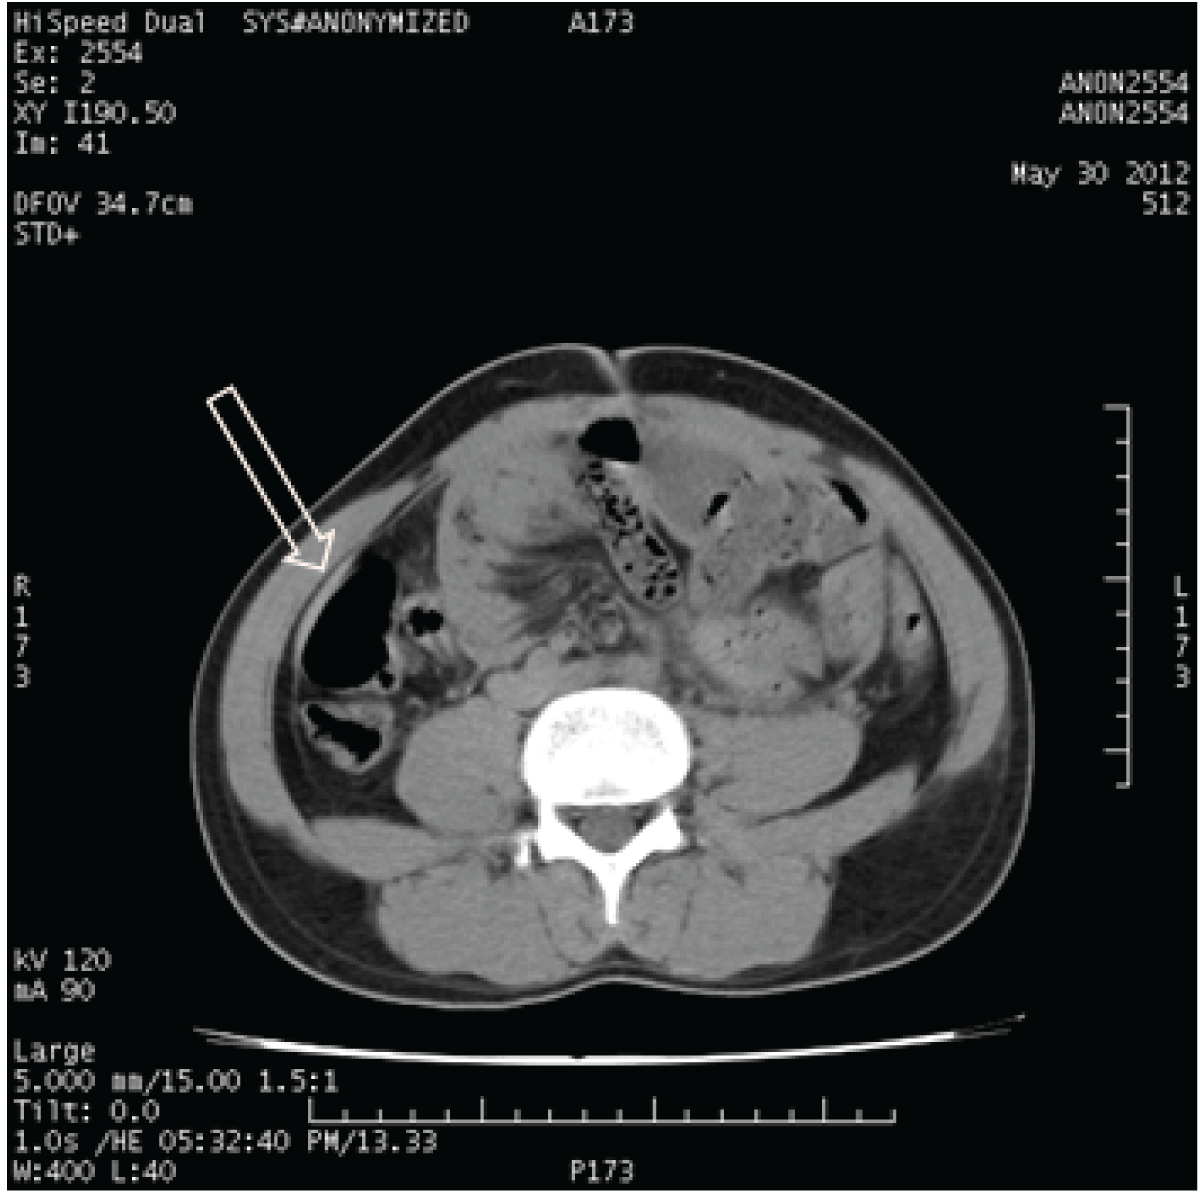

A 30-year-old male presented with vague complains of intermittent abdominal pain and back pain, nausea, vomiting and abdominal distension. He had undergone laparoscopic appendectomy five months ago. He had been having similar complaints before and after the surgery. No records about the operative findings in the previous surgery were available with the patient. On examination, his abdomen was distended with generalized tenderness in all quadrants. No free fluid in the abdomen made out on clinical examination. No mass or hernia was present in port sites. On auscultation, bowel sounds were sluggish. Initially the diagnosis was suspected as adhesive obstruction and was started on conservative management without symptomatic relief even after 12 hours. Blood counts were within normal limits. Computed tomography (CT) scan of abdomen showed all small bowel loops except duodenum and distal ileal loops were encased within a sac like structure with various thickness and small bowel showed signs of obstruction but no radiological evidence of mesenteric ischemia and suggested it to be a case of internal hernia or abdominal cocoon. (Figure 1) Radiologist suggested patient to be a case of internal hernia or abdominal cocoon causing intestinal obstruction. Since patient did not respond well for conservative management, he was taken up for laparotomy. Per operatively thick membrane noted just after opening up the parietal peritoneum which had to be opened to visualize intestines. Inner aspect of entire peritoneal cavity, both parietal and visceral peritoneum was covered with a membrane of variable thickness and in some places membrane was adherent causing intestinal obstruction. (Figure 2) Membrane causing obstruction were released with sharp dissection (Figure 3) and samples taken by peeling off the membrane from small bowel for biopsy. (Figure 4) Since entire peritoneal cavity was covered with membrane, it could not be totally removed. (Figure 5) Postoperative period was uneventful. Histopathological examination of the membrane showed nonspecific inflammatory cells with fibrosis.

Figure 1: Computed tomography scan of abdomen. The arrow shows the membrane lining the peritoneum.